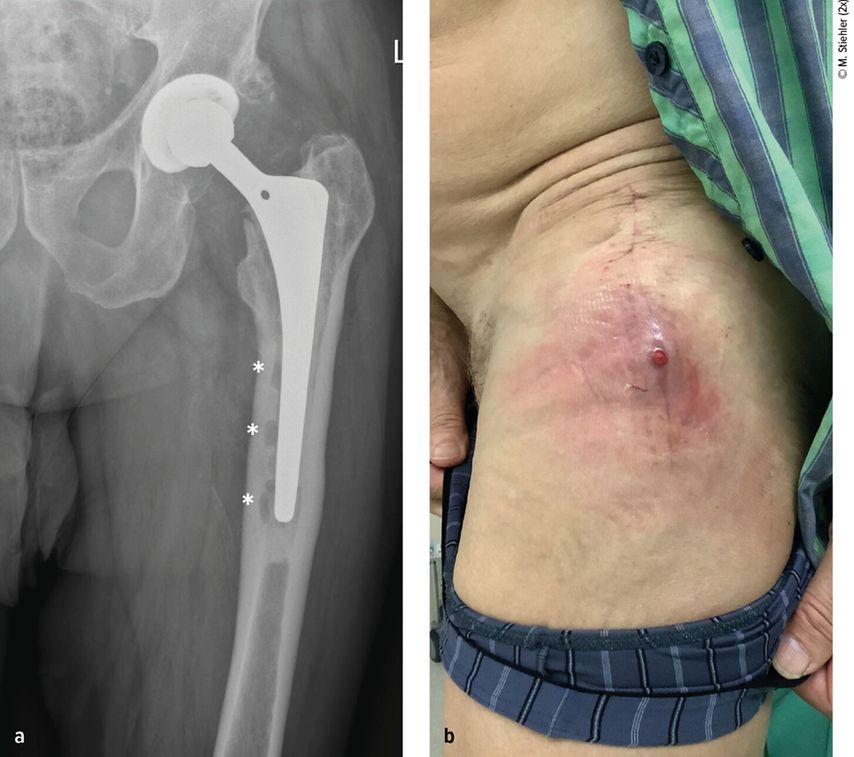

Abb. 1: Patient mit chronischer Hüftendoprotheseninfektion. Radiologisch zeigen sich infektionsbedingte periprothetische Osteolysen (*, a) und klinisch imponiert eine kutane Fistel (b).

Anhand der klinischen Zeichen und der Symptomdauer unterscheidet man zwischen akuter und chronischer PPI. Die akute PPI ist durch eine kurze Symptomdauer (<3 Wochen) charakterisiert. Sie tritt entweder in der frühen (<4 Wochen) Phase nach endoprothetischem Gelenkersatz (akute postoperative PPI) oder aber verzögert (>4 Wochen, ggf. erst mehrere Jahre) nach Endoprothesenimplantation im Rahmen einer hämatogenen Streuung eines endoprothesenfernen Infektionsherdes (akute hämatogene PPI) auf. Typischerweise imponieren hier lokale Infektionszeichen wie Schmerzen, Schwellung, Rötung, Überwärmung oder eine prolongierte Wundsekretion (>7 Tage). Die Unterscheidung zwischen akuter und chronischer PPI basiert auf den Eigenschaften des bakteriellen Biofilms. Beim Vorliegen einer akuten PPI ist von einem unreifen bakteriellen Biofilm auf der Endoprothesenoberfläche auszugehen. Bei der chronischen PPI (>4 Wochen postoperativ) mit längerer Symptomdauer (>3 Wochen) liegt hingegen ein potenziell reifer Biofilm vor. Die klinischen Symptome sind in der Regel weniger ausgeprägt. Jedoch kann das Vorliegen einer kutanen Fistel oder von radiologischen Zeichen der Endoprothesenlockerung auf eine chronische Infektion hinweisen (z. B. Abb. 1).